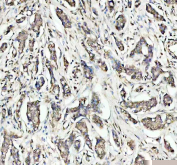

IHC staining of FFPE human lung cancer tissue with OGG1 antibody. HIER: boil tissue sections in pH8 EDTA for 20 min and allow to cool before testing.